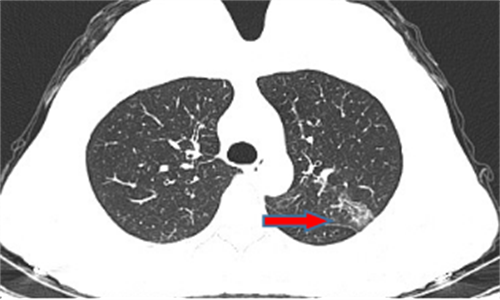

王女士,57岁,体检发现右下肺结节2月,术后病理诊断肺结节为肺隐球菌病。

郭女士,63岁,体检发现右下肺结节20天,术后病理诊断肺结节为浸润性腺癌。

王女士,65岁,体检发现右上肺磨玻璃结节16天,术后病理诊断肺结节为浸润性腺癌。

王女士,52岁,体检发现右上肺磨玻璃结节7月,术后病理诊断肺结节为原位腺癌。

王女士,35岁,新冠核酸检查阳性7天,胸部CT检查左上肺磨玻璃影,考虑新冠病毒性肺炎。